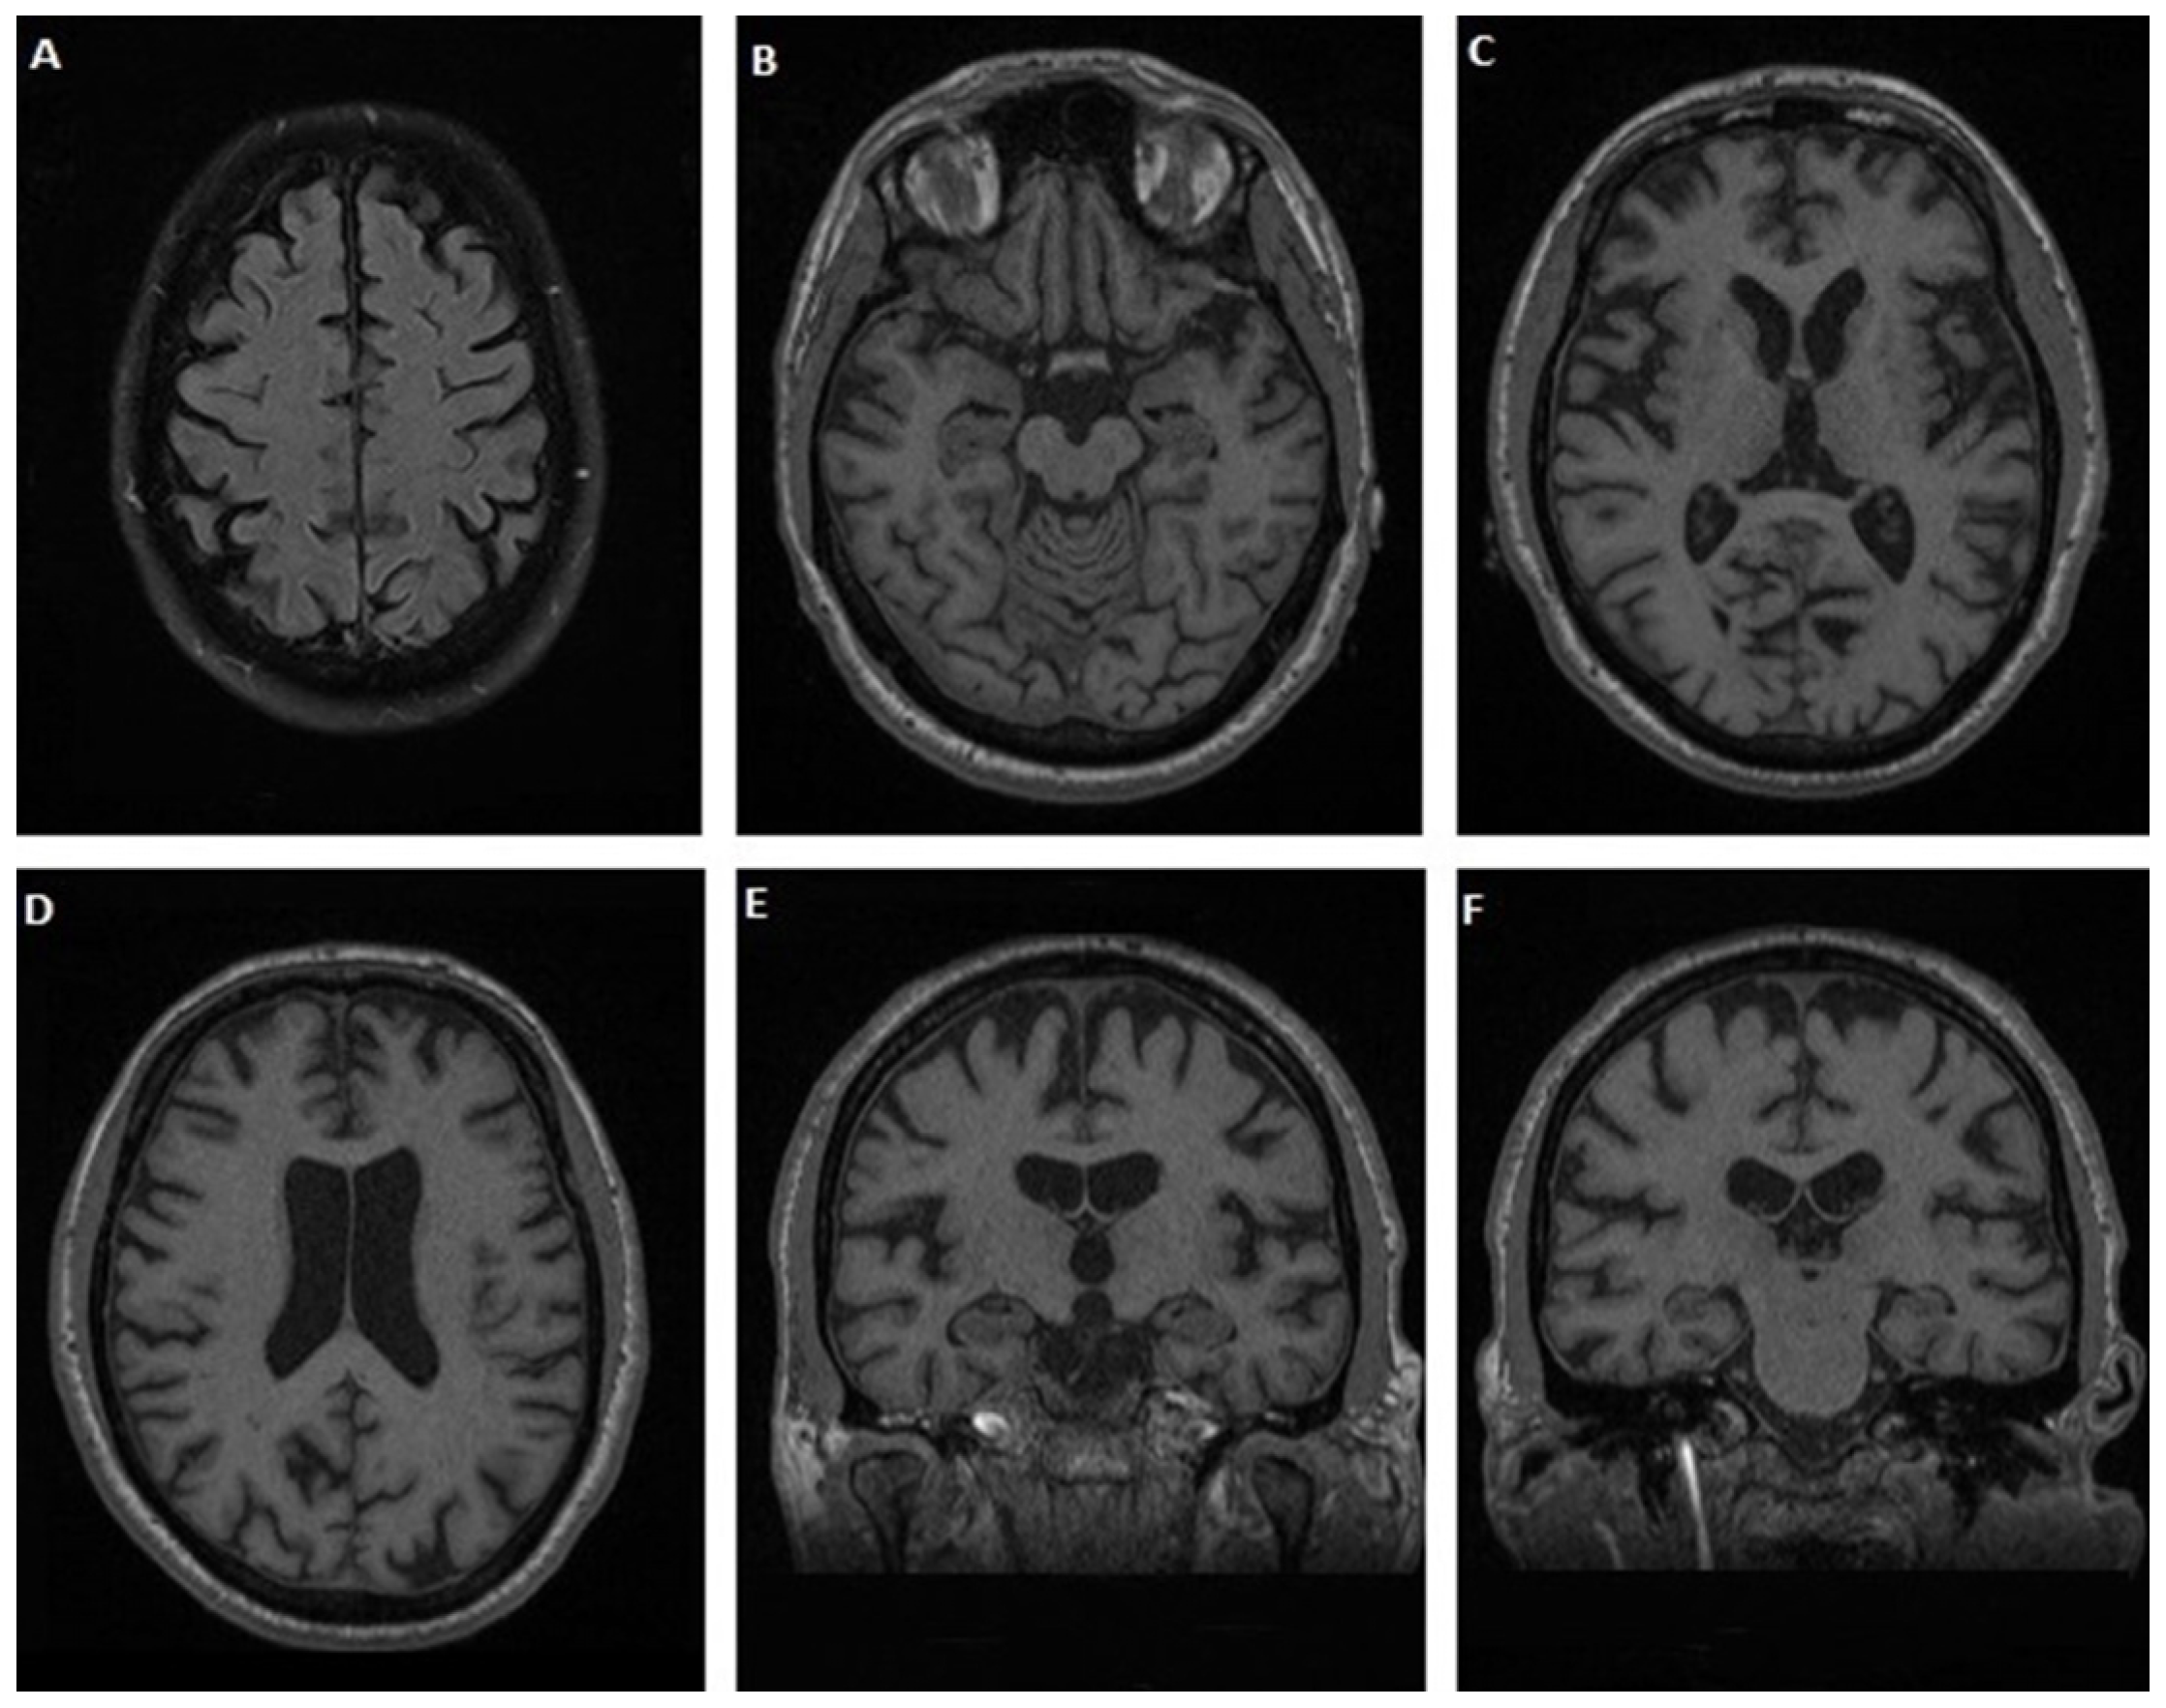

3.1.1. Case 1

3.1.2. Case 2

3.1.3. Case 3

3.1.4. Case 4

3.1.5. Case 5

3.1.6. Case 6